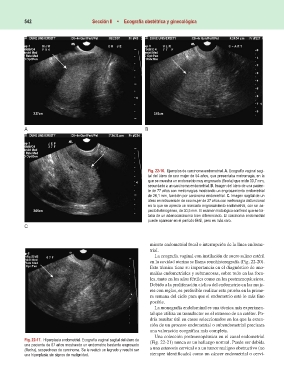

Fig. 22-16. Ejemplos de carcinoma endometrial. A. Ecografía vaginal sagi-

tal del útero de una mujer de 54 años, que presentaba metrorragia, en la

que se muestra un endometrio muy engrosado (flecha) que mide 33,7 mm,

secundario a un carcinoma endometrial. B. Imagen del útero de una pacien-

te de 77 años con metrorragias mostrando un engrosamiento endometrial

de 26,1 mm, también por carcinoma endometrial. C. Imagen sagital de un

útero en retroversión de una mujer de 37 años con metrorragia disfuncional

en la que se aprecia un marcado engrosamiento endometrial, con un as-

pecto heterogéneo, de 30,5 mm. El examen histológico confirmó que se tra-

taba de un adenocarcinoma bien diferenciado. El carcinoma endometrial

puede aparecer en el período fértil, pero es más raro.